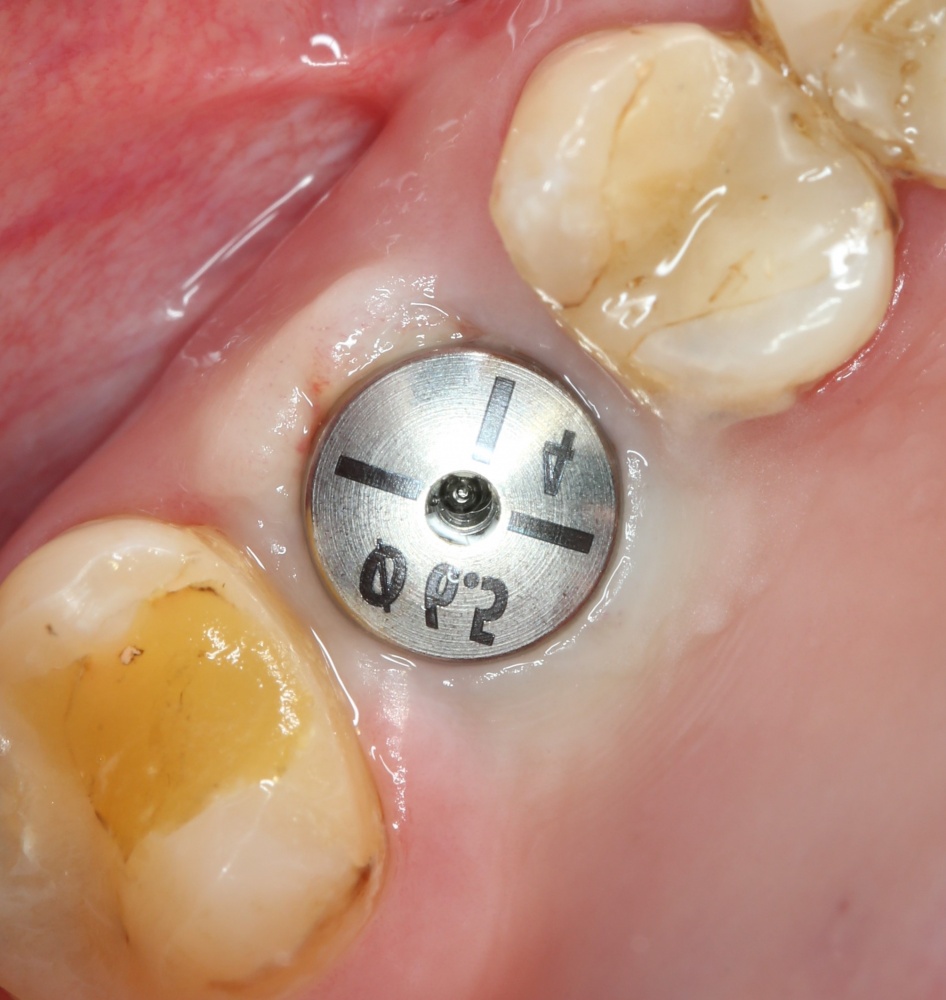

На приведенных фотографиях заметно, как изменились линейные размеры альвеолярного гребня с момента удаления 26 и установки импланта, до его интеграции (сравните толщину). Но это не так критично, и позволяет получить хороший результат протезирования:

Однако, если одной из задач имплантологического лечения является максимальное сохранение окружающих зуб тканей, то без использования биоматериалов вряд удастся обойтись. На фотографии ниже: вроде как, проведена немедленная имплантация, но последующая атрофия альвеолярного гребня вконец испортила эстетический результат лечения.